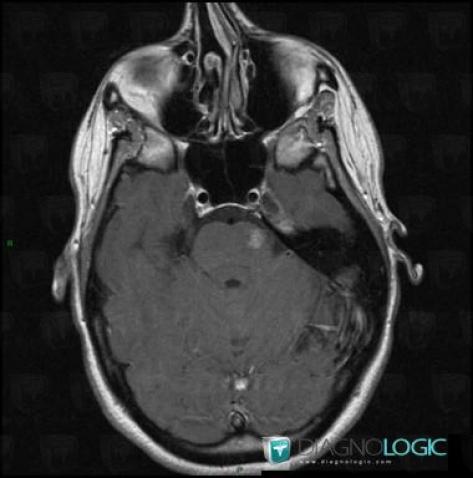

Télangiectasie capillaire, Fosse postérieure, IRM

Voici les informations spécifiques à l'image clé ci dessus:

- Diagnostic Télangiectasie capillaire, Localisation(s) Fosse postérieure, comportant les gammes